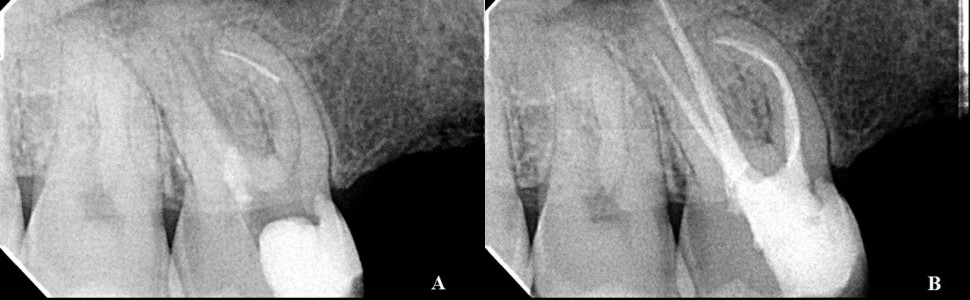

Złamanie narzędzi należy do powikłań, które występują podczas opracowywania kanałów korzeniowych. Wśród metod leczenia wyróżnia się podejście zachowawcze lub chirurgiczne. Celem poniższego opisu przypadków jest prezentacja zachowawczego podejścia w przypadku złamania instrumentów endodontycznych.

File’s separation is one of the complications that may occur during the shaping of root canals. The treatment methods cover a conservative or a surgical approach. The purpose of the following case reports is to present a conservative method in the management of broken endodontic instruments.